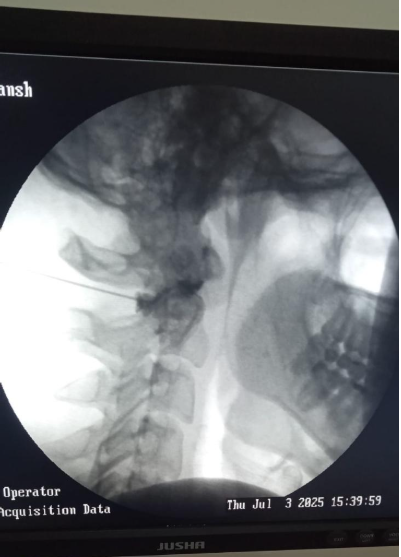

Fluoroscopy guided Intrartcular C1-C2 cervical facet joint anti inflammatory injection at Alleviate Pain Clinic, Bengaluru. Image Courtesy- Alleviate Pain Clinic

1. Cervical Facet Joint Injection

Mechanism of Action

- Steroid reduces inflammation inside the facet joint

- Local anesthetic breaks pain signaling

Indications

- Facet joint arthritis

- Neck pain worsened by extension or rotation

- Localized unilateral neck pain

Contraindications

- Active infection

- Bleeding disorders

- Unclear diagnosis